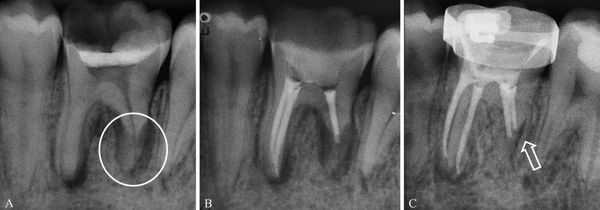

Повторные идентичные рентгенограммы травмированного зуба, сделанные через различные промежутки времени, необходимы не только для динамического наблюдения за репаративными процессами, но и для уточнения диагноза. Это связано с тем, что непосредственно после травмы (несколько часов), если не наблюдается выраженной подвижности или изменения положения коронковой части зуба, линия перелома может не визуализироваться. С течением времени происходит смещение отломка, связанное с усилением отека окружающих тканей и механического воздействия на коронку при жевании, щель между отломками расширяется и становится отчетливо заметной на снимке (рис. 10) .

Рис. 10. Внутриротовые снимки зуба 21: а — через час после травмы, б — через сутки.

При этом виде травмы зуб может перемещаться вестибулярно, орально, окклюзионно, в сторону соседних зубов или поворачиваться вокруг своей оси. При смещении зуба в вестибулярном или оральном направлении на рентгенограмме зуб проецируется более коротким по сравнению с соседним и нетравмированными зубами из-за того, что он наклонен. Проекция зуба будет тем меньше , чем больше его наклон. Изменяется и периодонтальная щель. Когда смещение зуба незначительное, периодонтальная щель расширена только у дна альвеолы. При значительном смещении имеет место расширение у верхушки и у боковых поверхностей

корня (рис. 1) .

Иногда неполный вывих в вестибулярную сторону сочетается с отломом альвеолярного края. На рентгене это выглядит как нарушение непрерывности кортикальной пластинки, ограничивающей лунку зуба, и в губчатой кости появляется полоска просветления (рис. 2) . При вывихе в сторону окклюзионной поверхности на рентгенограмме травми рованный зуб имеет ту же длину, что и соседний нетравмированный. Верхушка корня расположена к альвеолярному краю ближе, чем у соседнего нетравмированного зуба.

Периодонтальная щель расширена у всех поверхностей корня, особенно в области дна альвеолы. Кортикальная пластинка при этом виде вывиха не повреждается , и потому ее непрерывность не нарушается (рис. 3) .

Рис. 1. неполный вывих 21. На RG-грамме выглядит более коротким по сравнению с соседним нетравмированным 11. Имеет место расширение периодонтальной у верхушки и у боковых поверхностей корня.

Рис. 2. Вывих 12 с отломом альвеолярного края.

Рис. 3. Неполный вывих центрального резца в окклюзионном направлении.